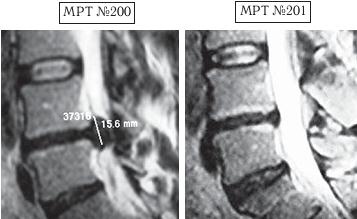

Пример № 5.

На МРТ № 200 наблюдается состояние поясничного отдела позвоночника после операции: рецидив — секвестрированная грыжа межпозвонкового диска в сегменте LIV-LV, абсолютный стеноз спинномозговогоканала.

На МРТ № 201 — состояние поясничного отдела позвоночника после лечения методом вертеброревитологии.